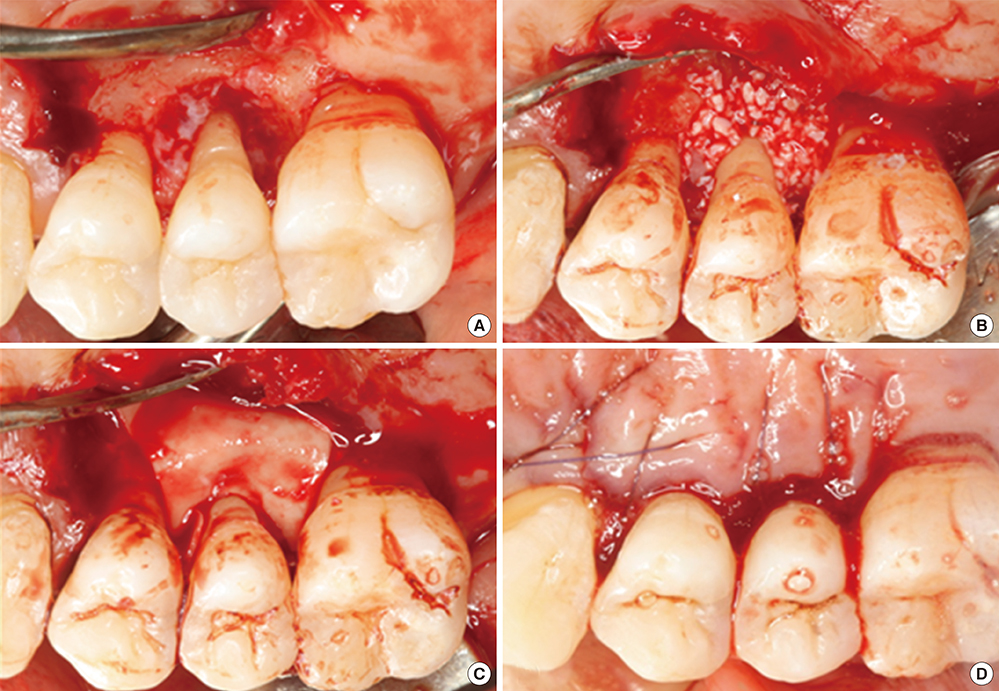

Hasarlı bölgeyi bir iskele ile doldurarak alveolar kemik de dahil olmak üzere kemik kaybını onarmak için vücudu uyarmayı amaçlayan birçok teknik vardır. Uygun iskele malzemesi, mezenkimal kök hücrelerin hasarlı bölgeye göç etmesini ve osteoblastlara farklılaşmasını sağlar. Bu yöntemi içeren ameliyatlar Güdümlü Kemik Rejenerasyonu veya Güdümlü Doku Rejenerasyonu (GTR) olarak adlandırılır. Bu prosedürler ile kemik grefti arasındaki en büyük fark, komşu dokunun hasarlı bölgeye doğru büyümesini önlemek için bir membran kullanılmasıdır.

Öncelikle yaralı bölgenin üzerine bir membran yerleştirilmelidir. Pamuklu gazlı bez bandajları gibi eski moda membranlar, patojenler ile açıkta kalan damar dokusu arasında bir bariyer oluşturur. Membranlar aynı zamanda epitel veya yara dokusu gibi diğer dokuların kayıp bölgeyi yanlış doku türüyle doldurmasını da engelleyebilir. Ancak pamuk, insan integrinlerine veya CAM'lerine bağlanan moleküller içermez ve bu nedenle bir iskele görevi görmez. Bir iskele olmadan, yaranın iyileşmesi yaranın kenarlarından gerçekleşir. Daha yeni malzemeler bu ders dizisinde ele alınan molekülleri içerebilir ve kök hücrelerin üzerinde göç ettiği bir iskele olarak kabul edilebilir. Bu moleküller ECM bileşenlerini veya morfojenleri içerebilir. Bazı morfojenler mezenkimal kök hücrelerin fibroblastlar (yara dokusu üreten) yerine osteoblastlara farklılaşmasını teşvik ederken, diğerleri anjiyogenezi teşvik etmek için kullanılabilir ve iyileşme sürecini hızlandırır.

Bir membran seçerken dikkat edilmesi gereken hususlardan biri, membranın emilebilir olup olmadığı veya çıkarılması gerekip gerekmediğidir (başka bir ameliyat gerektirir). Hem organik hem de sentetik polimerler rezorbe olabilir veya olmayabilir. Örneğin pamuk organiktir, ancak insan vücudu tarafından kolayca emilmez. Poli-laktik asit (PLA) membranlar (bunlar da organiktir, ancak laboratuvarda sentezlenir) iyileşme sürecinde kolayca emilir ve insan dokuları tarafından değiştirilir. Büyük moleküllerin rezorpsiyonu insan hücrelerinin aktivitesi olmadan da gerçekleşebilir. Örneğin PLA, ısı ve UV ışığına maruz kaldığında yavaşça bozulur. Diğer polimerler matriks metalloproteinazlar gibi insan enzimleri tarafından uzaklaştırılabilir. Güdümlü doku rejenerasyonu, hasarlı dokuların endodontik tedavideki lateks veya metal, porselen veya plastikten yapılmış bir dolgu gibi biyo-uyumlu ancak inert bir malzeme ile değiştirilmesinden kavramsal olarak çok farklıdır. Amaç bir boşluğu doldurmak değil, bir boşluğun iyileşmesini teşvik etmektir.